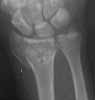

This 30 year old man sustained comminuted fracture shaft and undisplaced fracture neck of humerus. He has also technically compound fracture Distal Radius with intra-articular extension, but joint surface is congruent in the same upper limb. At present wound debridement POP immobilisation done. Options for management in this case? I am inclined to continue conservative management.

Presently I did closed reduction and Plaster cast immobilisation. Post reduction Xrays are attached. Do you think this will slip subsequently ?